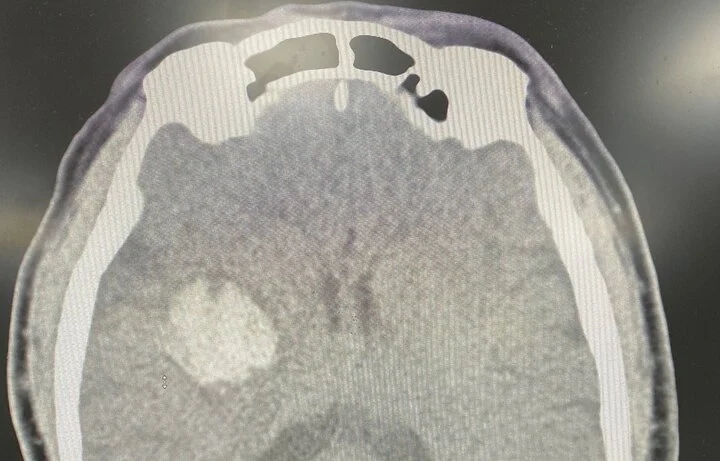

Sau uống thuốc các triệu chứng không cải thiện, thậm chí còn nặng hơn. Người đàn ông được gia đình đưa đến viện chụp cắt lớp vi tính sọ não dựng hình mạch máu não (CTA), kết quả hình ảnh xuất huyết não vùng nhân xám trung ương phải.

Hình chụp cắt lớp vi tính sọ não của bệnh nhân. (Ảnh: BVCC)